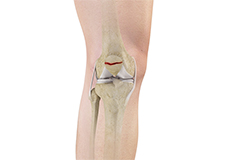

Bones of the Knee

The knee is a hinge joint made up of two bones, the thighbone (femur) and shinbone (tibia). There are two round knobs at the end of the femur called femoral condyles that articulate with the flat surface of the tibia called the tibial plateau. The tibial plateau on the inside of the leg is called the medial tibial plateau and on the outside of the leg, the lateral tibial plateau.

The two femoral condyles form a groove on the front (anterior) side of the knee called the patellofemoral groove. A small bone called the patella sits in this groove and forms the kneecap. It acts as a shield and protects the knee joint from direct trauma.

A fourth bone called the fibula is the other bone of the lower leg. This forms a small joint with the tibia. This joint has very little movement and is not considered a part of the main joint of the knee.